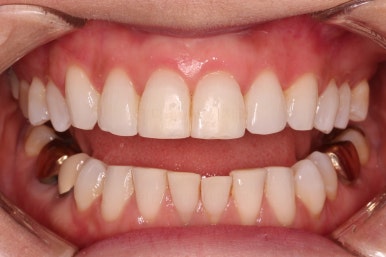

환자분이 원하시는 만큼 가지런해졌고, 부가적으로 생길 수 있는 부분들도 수용 가능한 선에서 잘 마무리가 되었습니다.

3개월이라는 빠른 기간 내에(심미보철 보다 약간만 더 긴 시간) 치아의 손상없이 마무리를 잘 했습니다.

아래 앞니는 부분교정까지는 원하지 않으셔서 약간 다듬어 드리고 종료했습니다.

이상 부분교정과 앞니 심미보철을 고민하셨던 분을 연산동부분교정 잘 개선했던 치료사례였습니다.